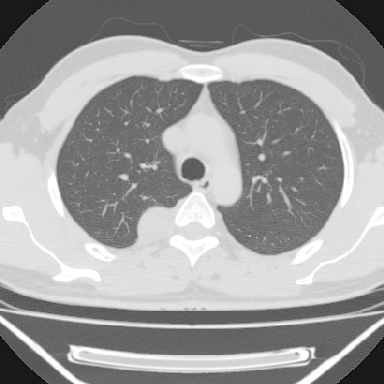

m 30 右胸痛10年

m,30岁,右胸痛10年。

右上后纵隔旁软组织肿块影,与肺界面光滑,与胸壁呈钝角相交,提示肺外病变。位于肋骨下缘,边缘清楚,呈三角样指向与右侧椎间孔,但并示进入椎间孔;与对侧神经根对比,属同一走行方向。

考虑后纵膈良性肿瘤,神经源性肿瘤可能大。

鉴别:胸膜来源肿瘤。影像表现虽有肺外征象,但无胸水等相应佐证;再者,病史前10年,超长,与胸膜肿瘤不太吻合。

建议:再次查体,问清疼痛部位,如为1~2个肋间痛则神经源性肿瘤可能大,如疼痛较弥散,不按肋间分布,则可能为后纵膈其它来源肿瘤。